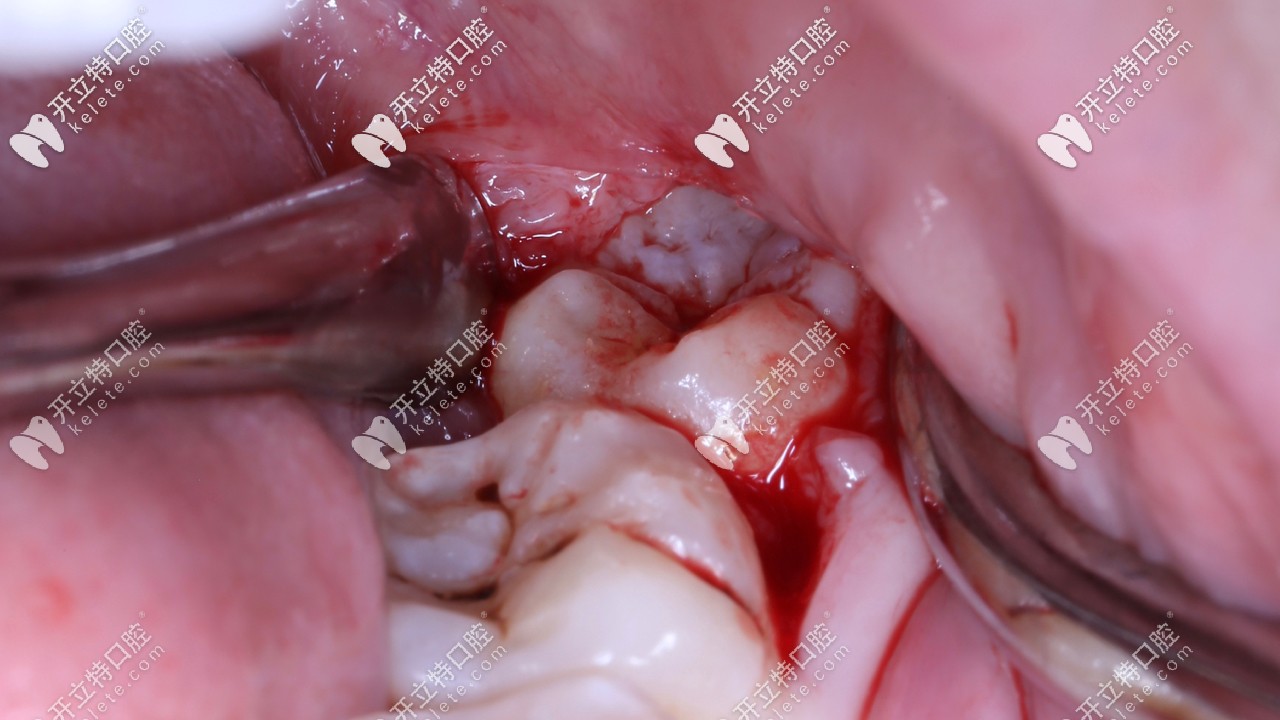

但是像我這長出一半,一半被肉包著,容易發(fā)生齲壞,而且反復(fù)感染痛疼,就需要拔除,像我這樣的需要切開齦瓣,當(dāng)時聽醫(yī)生這么說,真的感覺挺恐怖,??谖⑿谇蛔o(hù)士姐姐一再安慰我,拔牙是打麻藥的,拔的時候是感覺不到痛的。

打麻藥的時候有一點酸疼,針會直接插進(jìn)牙齦里。等了10分鐘左右麻藥很快就產(chǎn)生效果,整個右半邊臉是麻的,我特意用指甲使勁掐了下嘴唇,一點都不疼,麻藥起作用后就開吃拔牙,我都不知道什么時候牙齦被掀開,拔牙的時候用的鉗子,牙挺,錘子,不過沒敲幾下就聽到醫(yī)生說已經(jīng)松了,整個過程張著嘴,無感覺,男醫(yī)生力氣大,一拔就出來了。